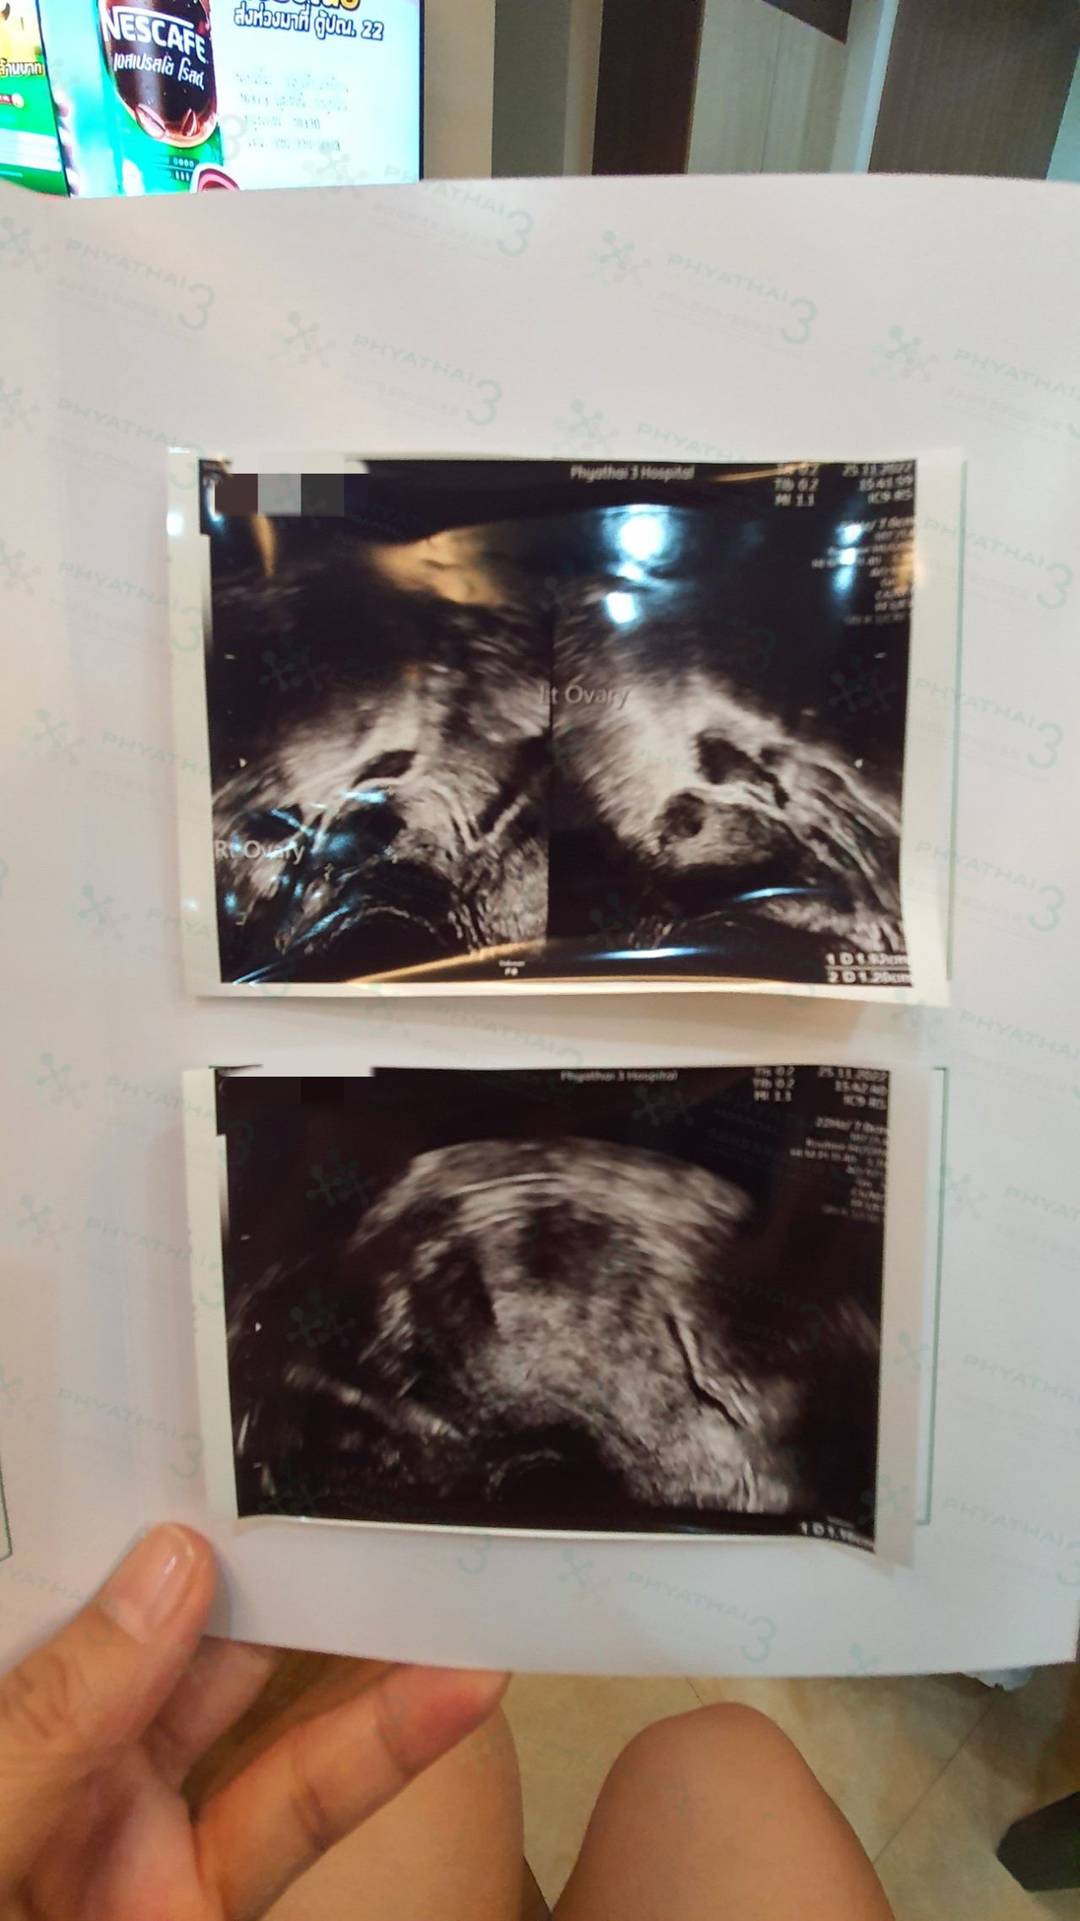

今天女士是取卵后第一次来月经的见诊,女士说这次的月经量比以往的都要多,是什么原因呢?医生说因为女士在促排后雌激素水平会升高,这个时候女性子宫内膜增厚,所以月经期间会出现月经量大的情况是正常现象。在激素分泌正常以后月经量逐渐恢复正常。

医生在阴超检查看到女士的卵巢里面还有空卵泡还没有消下去,所以医生让女士吃避孕药,控制卵泡大小让它消下去,从而促使卵巢环境更加稳定并调理月经周期,让下一轮月经提前来。